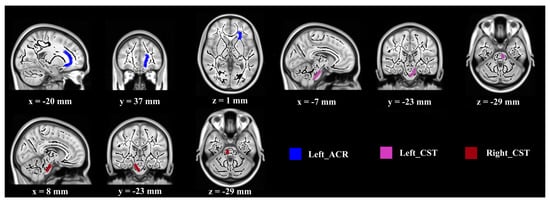

| WM Region | Control Group (n = 14) | Exercise Group (n = 15) | ||

|---|---|---|---|---|

| Baseline | Post-Test | Baseline | Post-Test | |

| Fractional Anisotropy | ||||

| Body of corpus callosum | 0.557 ± 0.031 | 0.551 ± 0.038 | 0.556 ± 0.024 | 0.497 ± 0.051 |

| Fornix | 0.477 ± 0.078 | 0.463 ± 0.078 | 0.479 ± 0.055 | 0.654 ± 0.025 |

| Right cerebral peduncle | 0.621 ± 0.024 | 0.617 ± 0.042 | 0.637 ± 0.031 | 0.672 ± 0.025 |

| Left posterior limb of internal capsule | 0.656 ± 0.024 | 0.653 ± 0.034 | 0.658 ± 0.025 | 0.672 ± 0.019 |

| Right retrolenticular part of internal capsule | 0.557 ± 0.018 | 0.553 ± 0.023 | 0.561 ± 0.043 | 0.582 ± 0.030 |

| Left anterior corona radiate | 0.390 ± 0.025 | 0.388 ± 0.031 | 0.393 ± 0.028 | 0.415 ± 0.029 |

| Left superior fronto-occipital fasciculus | 0.446 ± 0.029 | 0.436 ± 0.033 | 0.450 ± 0.024 | 0.469 ± 0.041 |

| Mean Diffusivity (10−3 mm2/s) | ||||

| Left corticospinal tract | 0.799 ± 0.059 | 0.833 ± 0.012 | 0.805 ± 0.072 | 0.761 ± 0.076 |

| Right corticospinal tract | 0.793 ± 0.037 | 0.824 ± 0.010 | 0.799 ± 0.072 | 0.744 ± 0.080 |

| Left anterior corona radiate | 0.866 ± 0.461 | 0.871 ± 0.069 | 0.858 ± 0.047 | 0.820 ± 0.048 |